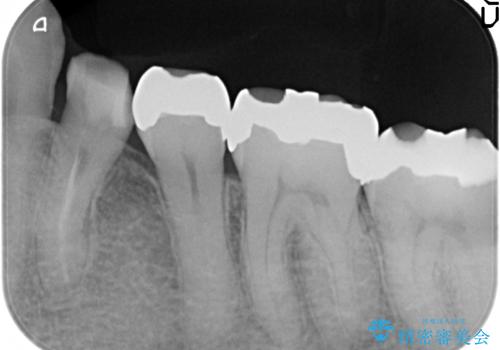

- 左下の詰め物が取れてしまったので治療したい、ついでに銀歯も白くしたいといらっしゃった方の症例です。

銀歯及び虫歯を除去後、オールセラミッククラウンによる補綴を行いました。

今回用いたオールセラミッククラウンはジルコニアフレームという白い素材の上にセラミックを盛っているため、審美性が非常に高いのが特徴です。

また、ジルコニアは人工ダイヤモンドの材料にも使われているほど高い強度を持っており、そのためオールセラミッククラウンは審美性だけでなく、奥歯やブリッジの補綴も可能とするクラウンです。